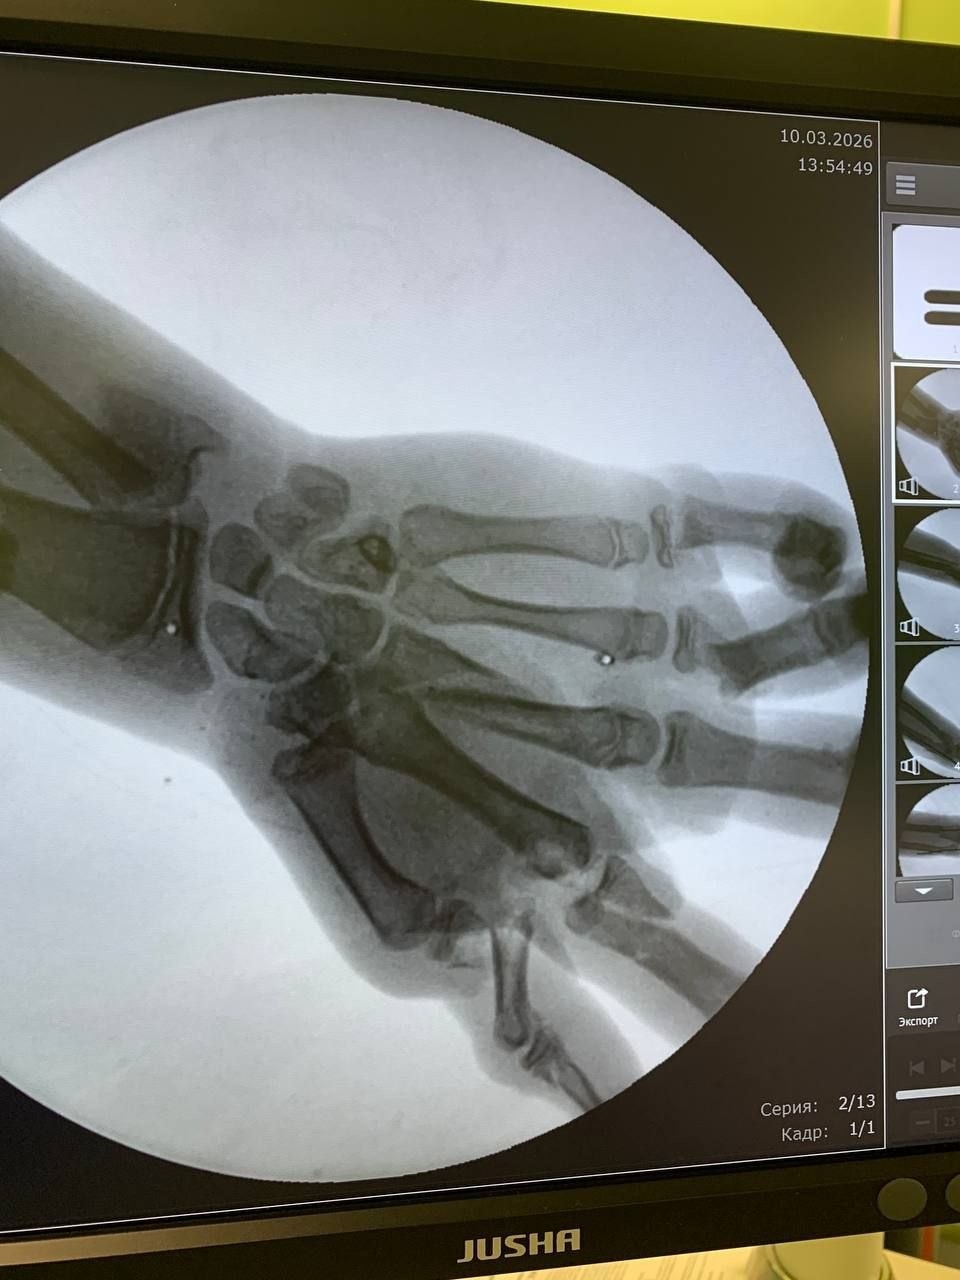

В медицинское учреждение юный пациент поступил в шоковом состоянии. Врачи констатировали у него перелом нижней трети левого предплечья со смещением, раны на левой голени и лбу, но самым опасным стало травмирование левой кисти. Взрыв спровоцировал множественные переломы костей и сильное кровотечение, риск потери части конечности был весьма высок, — рассказали в Минздраве.

Мальчика прооперировали хирурги-травматологи. Отмечается, что медики буквально собрали кисть ребёнка по частям. Первое вмешательство длилось полтора часа и прошло успешно.

«Через несколько суток, оценив зону некроза, которая благодаря своевременно обеспеченному кровотоку в кисти оказалась небольшой, мы провели мальчику вторую, восстановительную операцию. Во время неё с помощью пластики были устранены дефекты тканей и костей», — рассказал хирург-травматолог Александр Гозун.

Фото: региональный Минздрав